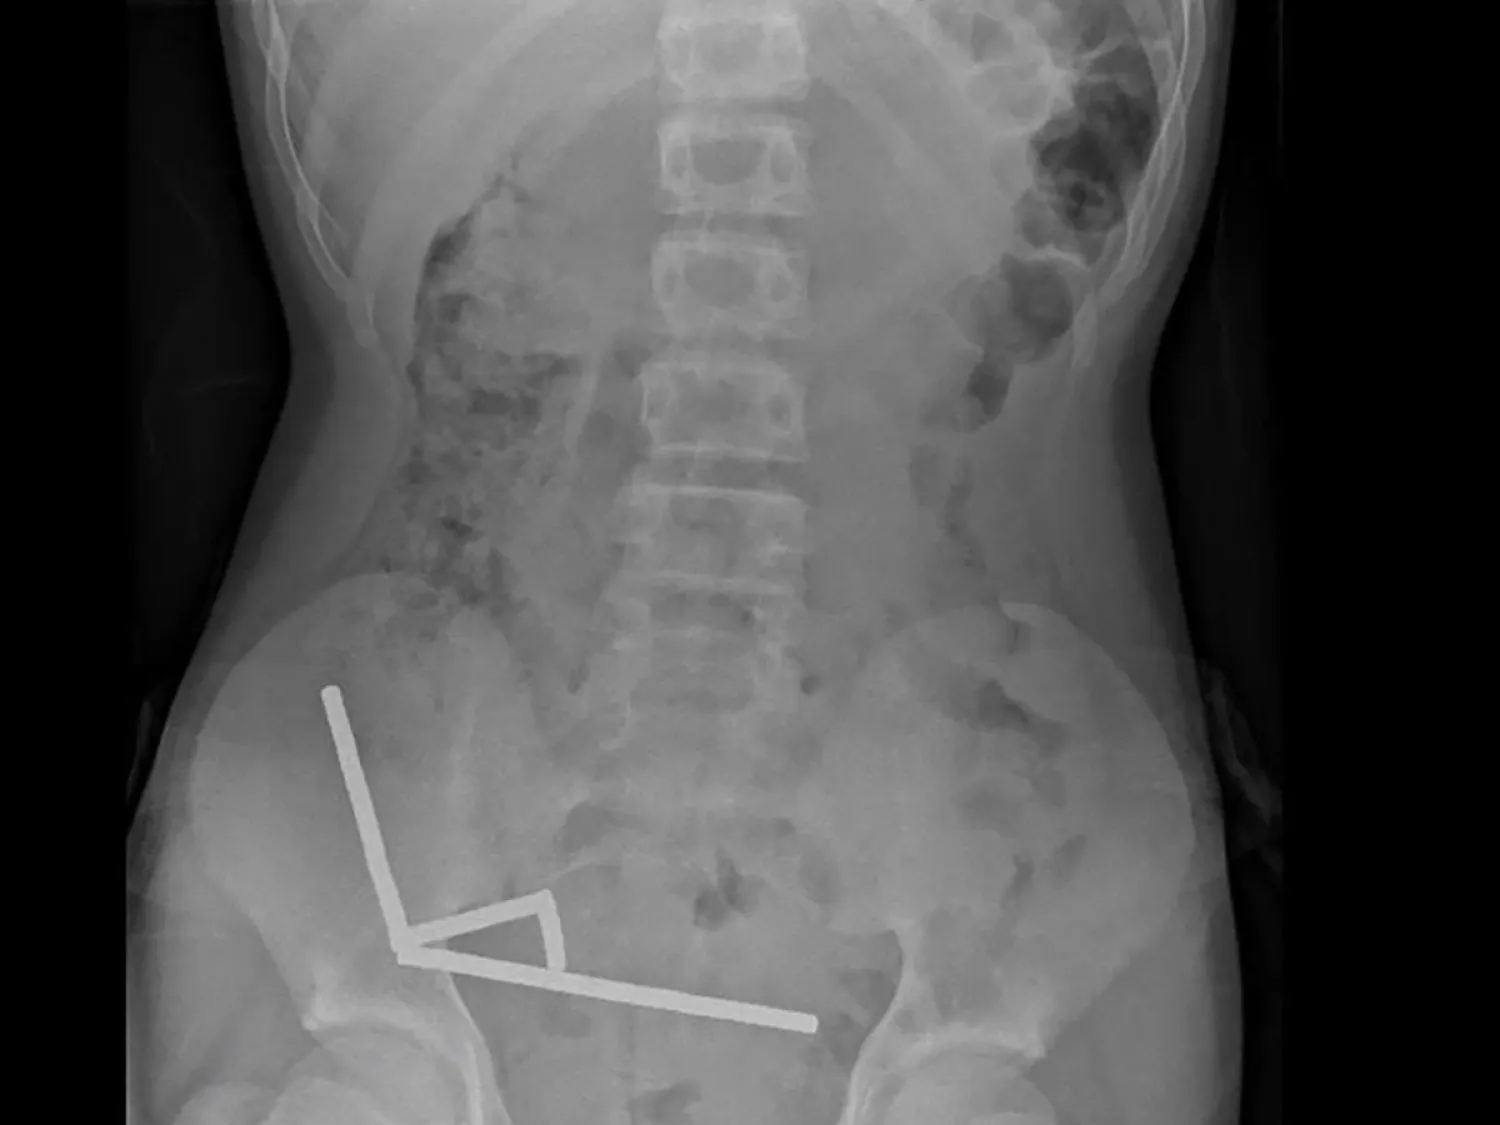

وأظهرت الأشعة السينية أنّ المغانط تجمّعت على شكل أربع خطوط مستقيمة داخل أمعاء الصبي.

وقال الأطباء: «يبدو أنّ هذه المغانط كانت في أجزاء منفصلة من الأمعاء التصقت ببعضها البعض بسبب القوى المغناطيسية».